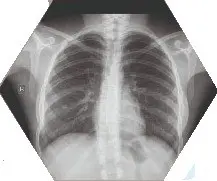

Imagenologia